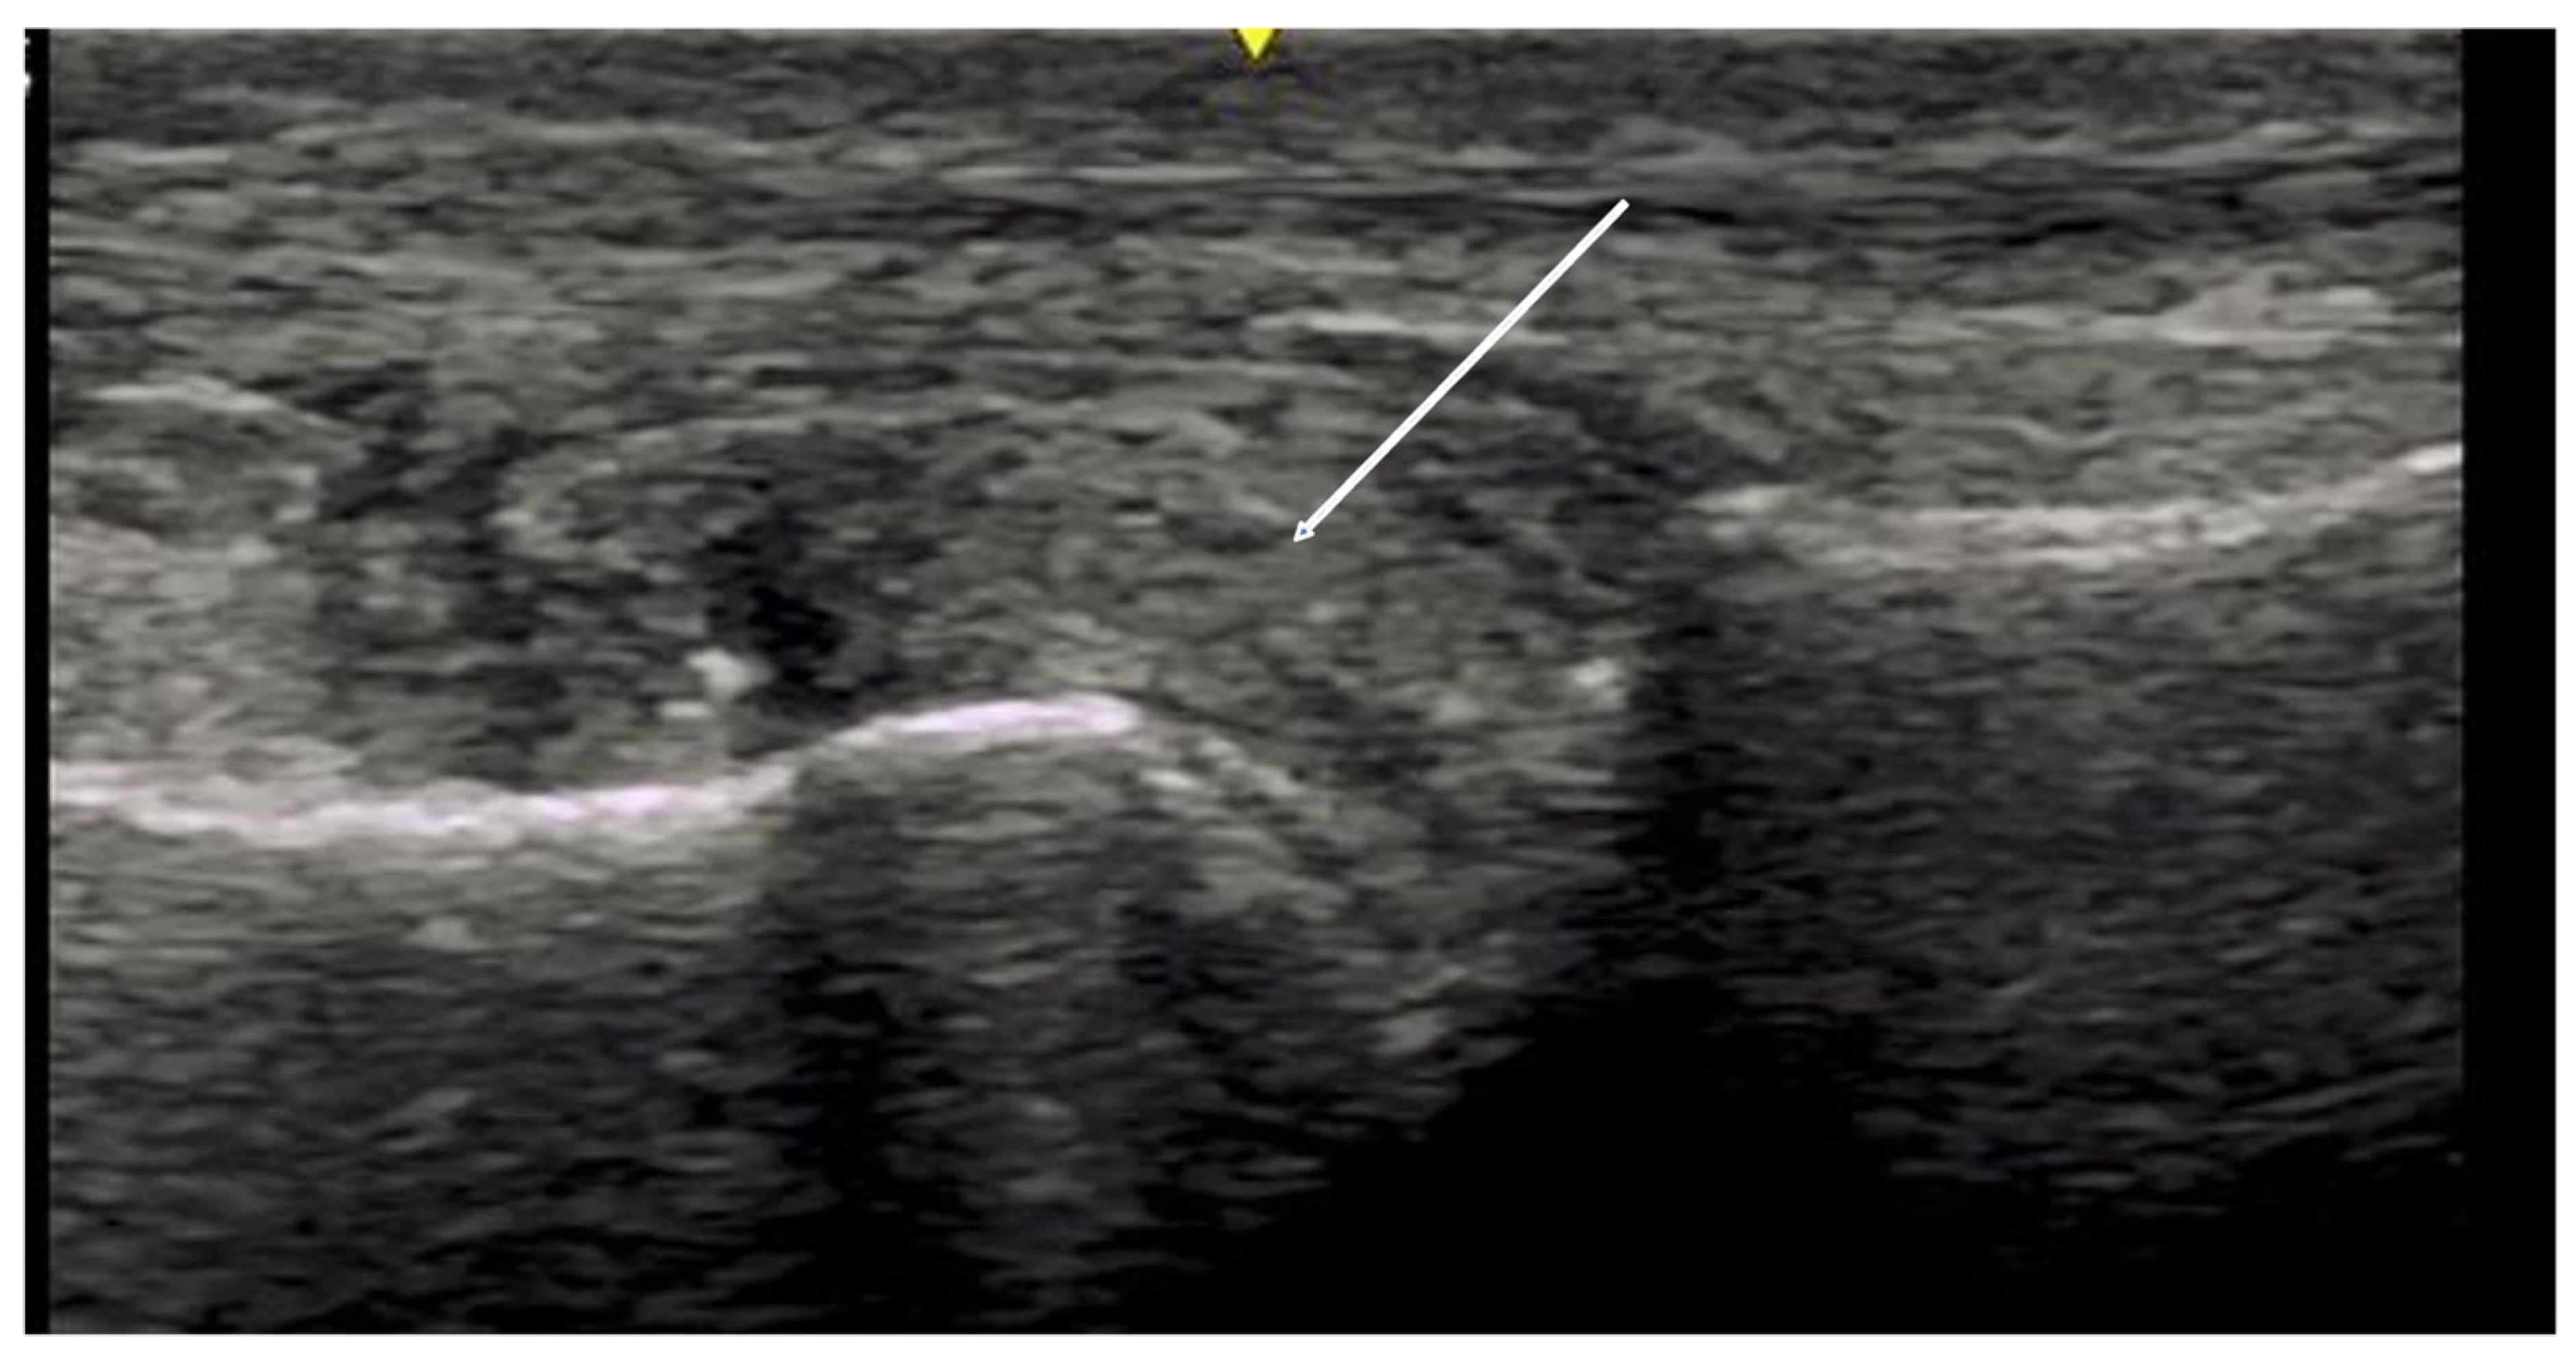

2.2.2. Contractures and Tendon Friction Rubs

4.2. Evaluation of the Wrist

4.2.3. Ulnar Aspect